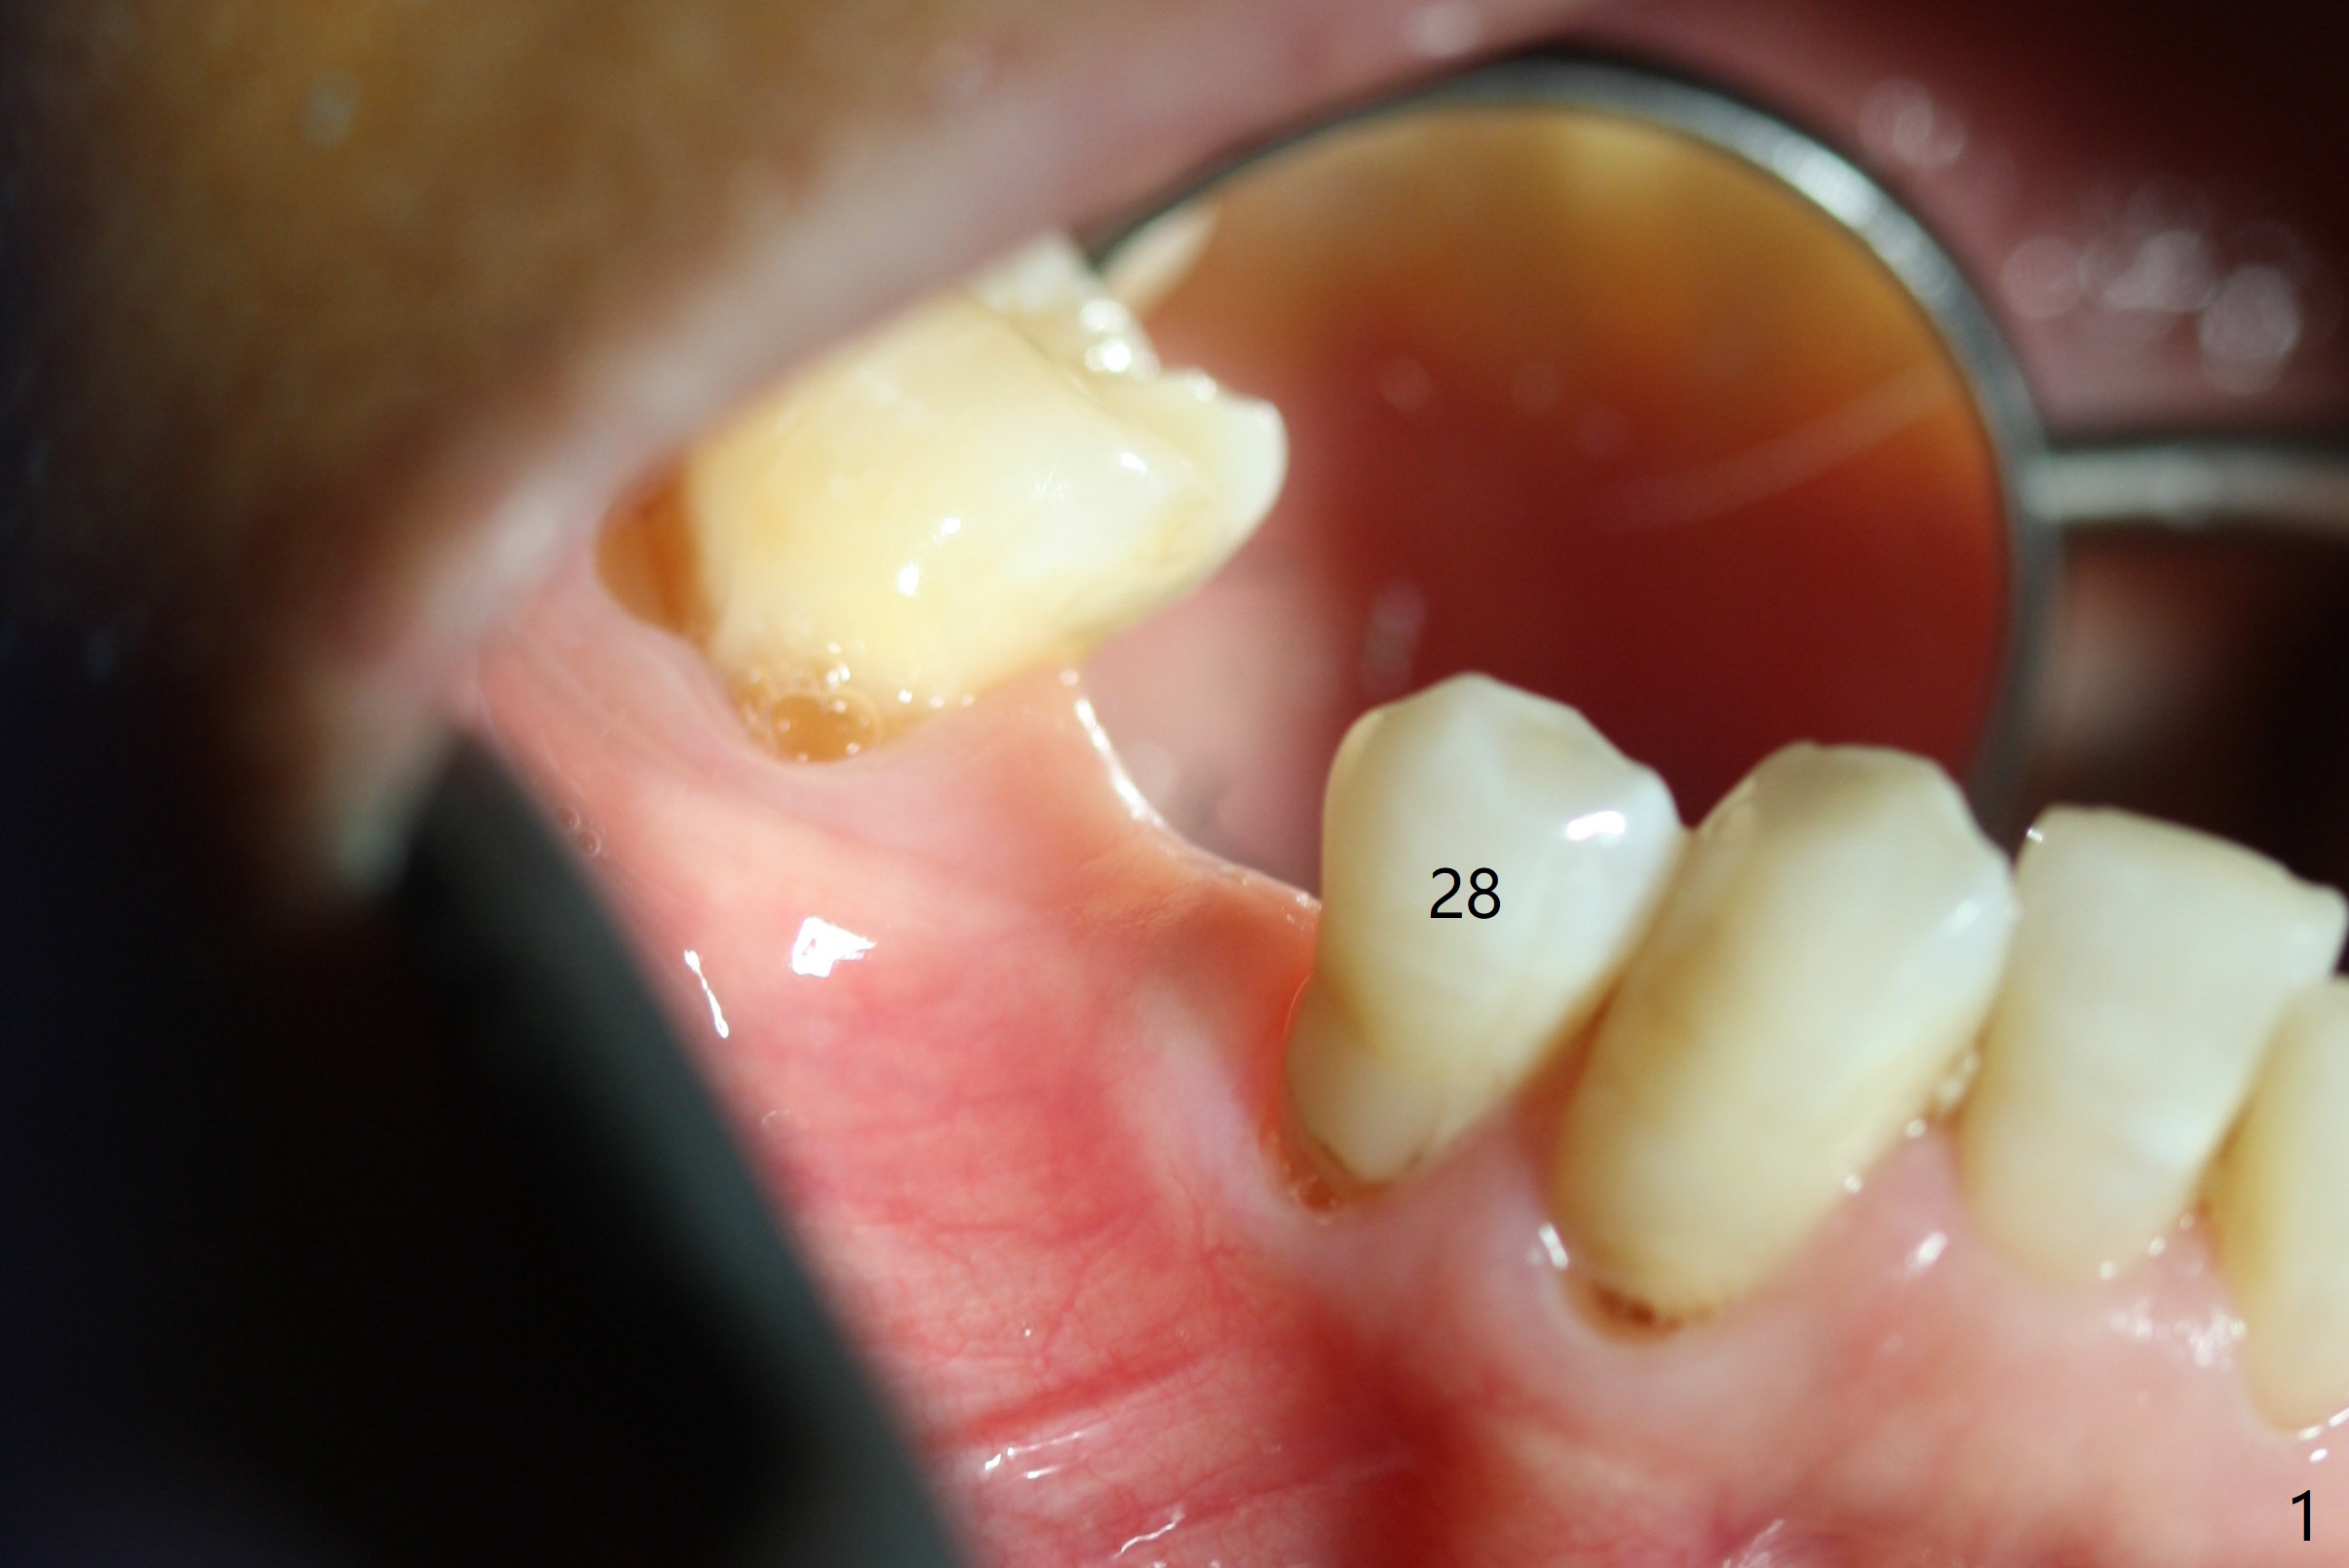

After incision the ridge at #29 is not so narrow as shown in Fig.1. But it is still intact, in contrast to what CBCT shows. Osteotomy is initiated with 1.2 mm drill, followed by 1/1.6, 1.3/2.3 and 1.7/3.1 mm DIO Bone Expanders. In fact mesial and distal crestal slots (BEB: bone expansion and bending) are created by using surgical fissure bur in order to insert the last bone expander in place (10 mm, Fig.2). Following 3.5 mm Cortical Tap, a 3.5x10 mm IS Implant is placed ~ 50 Ncm with clearance from the Mental Loop (Fig.3,4 red dashed line) and slightly subcrestal (Fig.5). The most distal part of the distal slot created for BEB is shown in Fig.5 *. Bone resorption is minimal 4 months postop (Fig.6,7). The implant was apparently placed in the middle buccolingually (Fig.8).